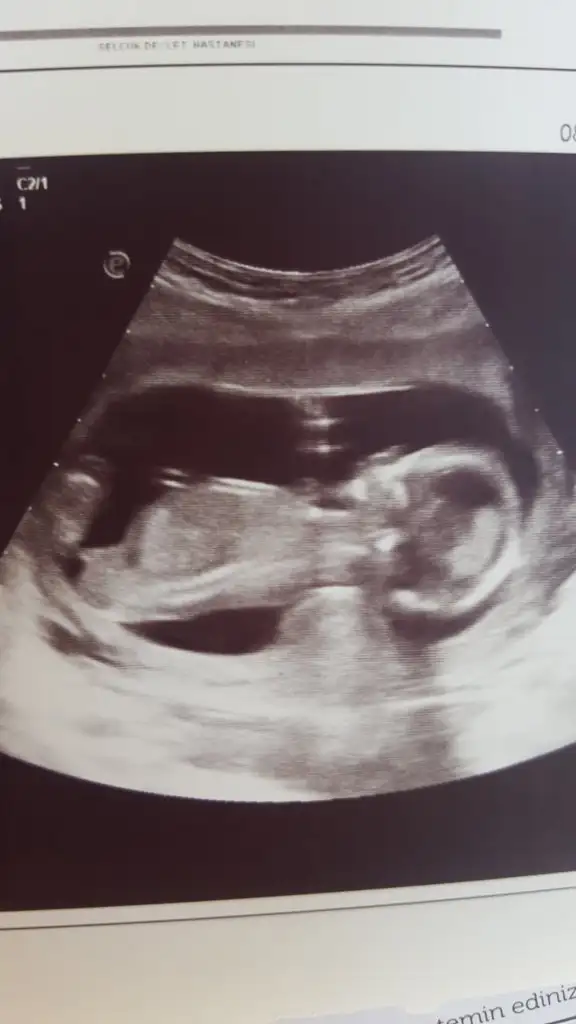

Bizde 11+5 olduk. Bizim bu görüntüyüde bakarmısınız![]()

Arada kaldım ama kız gibi geldi bana Canım doktorun tahmin de bulundu muArkadaşlar yorum yapabilir misiniz 14 haftalık 2 boyutlu vermedi